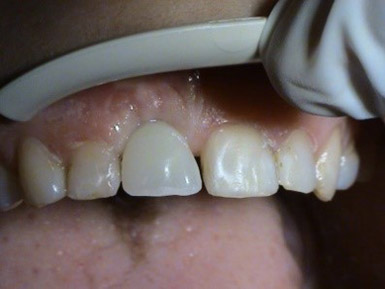

3. PHASE – prosthetic fabrication of temporary crown on implant

3. PHASE – fabrication of temporary solution